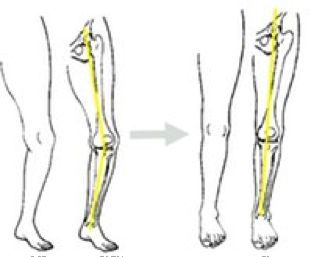

Una proporción elevada de las personas adultas presentan artrosis de rodilla, la cual es el resultado de un proceso degenerativo o por lesiones previamente sufridas en esta articulación. La artrosis de rodilla produce dolor y limitación funcional. Si bien la artrosis es tratada en estadíos y edades más avanzadas con el reemplazo articular con una prótesis de rodilla, en pacientes entre los 30 y los 60 años la osteotomía de rodilla es una alternativa a tener muy en cuenta.

Una osteotomía de rodilla es un procedimiento quirúrgico que se realiza en pacientes que tienen sólo un compartimiento de su rodilla afectado por artrosis (sobre todo en sus estadíos más iniciales), por lo general en la región medial o interna de la articulación. El objetivo principal de esta cirugía es mejorar la función, disminuir el dolor y retrasar la necesidad de colocar una prótesis. Es decir, busca alargar la vida útil de la articulación. Esto se logra por corregir el eje de la extremidad inferior afectada, desplazando la carga del peso hacia zonas de la rodilla que se encuentran sanas. Así, se aligera el peso que soporta la zona comprometida por la artrosis.